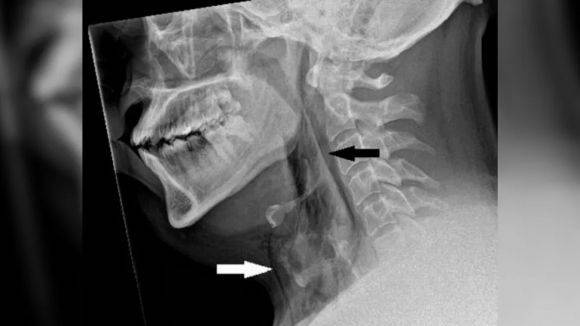

그는 호흡과 삼키기, 말하기에는 문제가 없었다. 다만 의료진이 엑스레이(X-ray)를 촬영하자 피부 아래 가장 깊은 조직층 아래에 공기가 갇히는 질환인 '폐 공기증'의 징후가 발견됐다. CT 스캔 결과 A씨 목의 세 번째와 네 번째 뼈 사이에 찢어짐이 생겨 기도에서 공기가 빠져나와 목 조직과 폐 사이 공간으로 들어간 것으로 확인됐다. 기도에 생긴 구멍의 크기는 지름 2㎜였다.